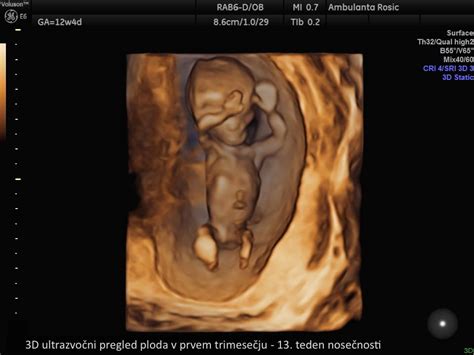

Prvo trimesečje nosečnosti, ki traja od 1. do 13. tedna, je obdobje hitrih sprememb tako za plod kot za bodočo mamico. Začne se z oplojeno jajčno celico, ki se skozi zapleten proces razvije v zarodek, nato pa v fetus z že v celoti oblikovanimi vitalnimi organi.

- 12. teden nosečnosti: Plod meri 5,4 cm (kot sliva) in tehta 14 g. Srce deluje kot pri odraslem, centralno živčevje pa se razvija. Maternica je velikosti grenivke. Imuniteta nosečnice se naravno zmanjša, kar koristi rastočemu plodu.

- 13. teden nosečnosti: Plod meri 7,4 cm (kot breskev) in tehta do 23 g. Glavica še vedno predstavlja polovico dolžine ploda, a okončine hitro rastejo. Jutranje slabosti se pogosto umirjajo, lahko pa se pojavi zgaga.

Pregledi v prvem trimesečju: Vključujejo laboratorijske analize (krvna slika, krvni sladkor, krvna skupina, Rh faktor, test na toksoplazmo in sifilis), ultrazvočno potrditev nosečnosti do 11. tedna ter pregled nuhalne svetline in dvojnega hormonskega testa med 11. in 14. tednom.